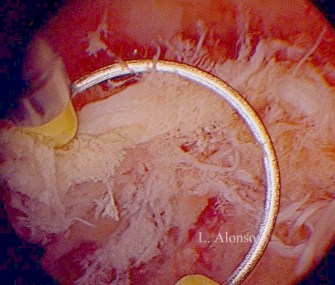

La histeroscopia nos permite la visualización directa del tejido retenido intrauterino así como la localización del mismo. Si no existe un sangrado abundante, puede ser realizada en consulta y nos permite la toma de biopsia

Debido a que la persistencia de restos suele ser focal, la extracción de los mismos bajo visión directa y de manera dirigida mediante la histeroscopia, nos parece la alternativa más segura y efectiva, superando a la extracción “a ciegas” de los restos, al disminuir la posibilidad de aparición de las complicaciones relacionadas con la realización del legrado uterino.